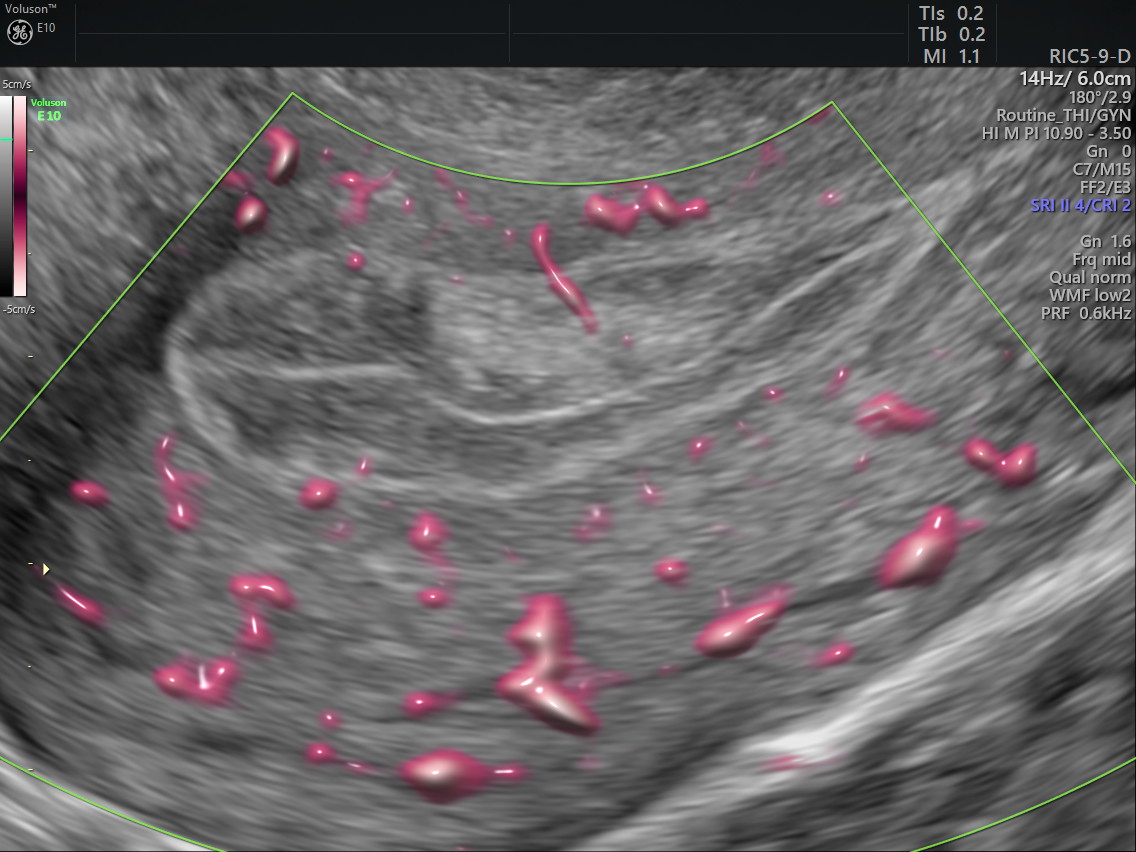

(A)

(B)

(C)

Imagem de ultrassom convencional mostrando pólipo (A), pólipo ao Doppler em cores (B) e ultrassom tridimensional VCI realçando o pólipo no endométrio (C).